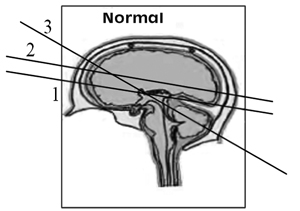

Οι βασικές απεικονίσεις του εγκεφάλου:(1,2,6,19)

- Διαθαλαμικό επίπεδο (1).

- Διακοιλιακό επίπεδο (2).

- Διαπαρεγκεφαλιδικό επίπεδο (3).

Α. Διαθαλαμική απεικόνιση

Β. Διαπαρεγκεφαλιδική απεικόνιση

Γ. Διακοιλιακή απεικόνιση